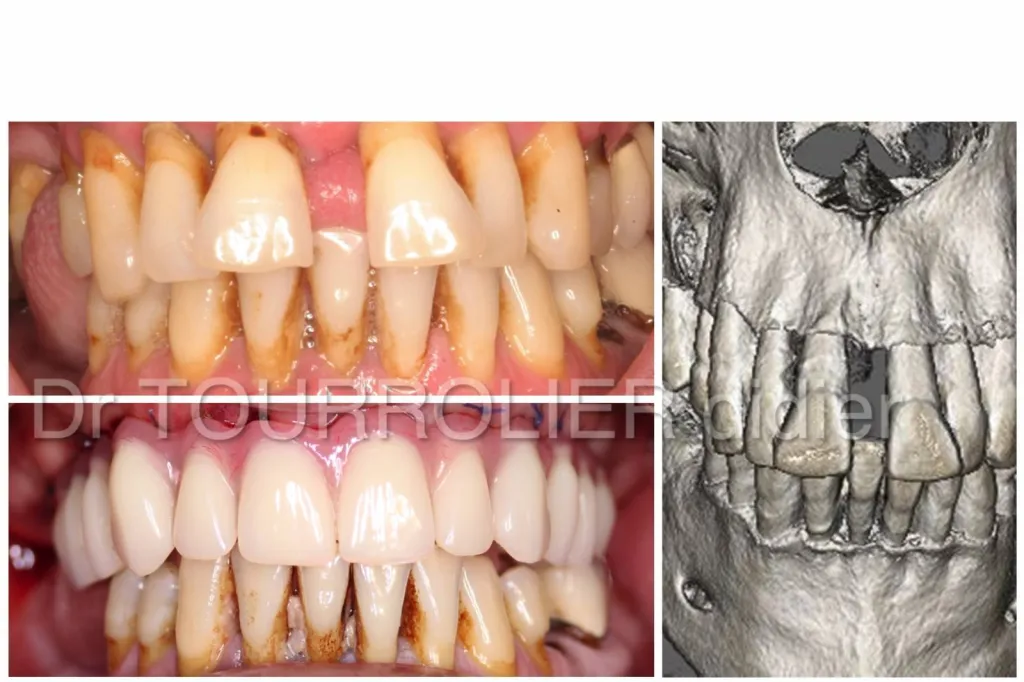

all-on-4 avant après. Dr Tourrolier Marseille

La technique all on 4 encore appelée Quattro permet de remplacer toutes les dents d'une Arcade en une journée par un appareil fixé sur 4 implants.